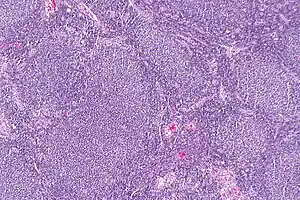

| Micrograph of a follicular lymphoma, showing the characteristically abnormal lymphoid follicles that gave the condition its name. H&E stain. | |

Follicular lymphoma (FL) is a cancer that involves certain types of white blood cells known as lymphocytes. The cancer originates from the uncontrolled division of specific types of B-cells known as centrocytes and centroblasts. These cells normally occupy the follicles (nodular swirls of various types of lymphocytes) in the germinal centers of lymphoid tissues such as lymph nodes. The cancerous cells in FL typically form follicular or follicle-like structures (see adjacent Figure) in the tissues they invade. These structures are usually the dominant histological feature of this cancer.[1]

The diagnosis of FL depends on examining involved tissues for histological, immunological, and chromosomal abnormalities that are indicative of the disease. FL usually involves enlarged lymph nodes populated by abnormal follicles (see adjacent picture) that when examined histologically contain a mixture of centrocytes or centroblast surrounded by non-malignant cells, mostly T-cells. The centrocytes, which typically outnumber centroblasts, are small to medium-sized B-cell lymphocytes that characteristically exhibit cleaved nuclei; the centropblasts are larger B-cell lymphocytes without cleaved nuclei.[11] Rare cases of FL may show lesions that contain tissue infiltrations dominated by B-cells with features of precursor (i.e. "blast") cells, monocytes, or malignant mantle cells such as those found in mantle cell lymphoma.[1] Immunochemical analyses reveal that these cells generally express B-cell surface markers including the CD10 (60% of cases), CD20, CD19, CD22, and CD79 but not CD5, CD11c, or CD23 cell surface proteins;[4] genomic analyses reveal that these cells contain t(14:18)(q32:q21.3) translocation (85-90% of cases), 1p36 deletions (60-70% of cases), and with far less frequency the other genomic abnormalities listed in the above sections on Pathophysiology and Presentation and course. None of these protein markers or genomic abnormalities are diagnostic for FL, e.g. the t(14:18)(q32:q21.3) translocation is found in 30% of diffuse large B-cell lymphoma and in a small number of reactive benign lymph nodes. Rather, the diagnosis is made by a combination of histological, immunological, and genomic abnormalities.[4] According to World Health Organization (WHO) criteria, differences in the microscopically determined morphology of these tissues can be used to diagnose and categorized FL into the following 3 Grades with grade 3 having A and B subtypes:[51]